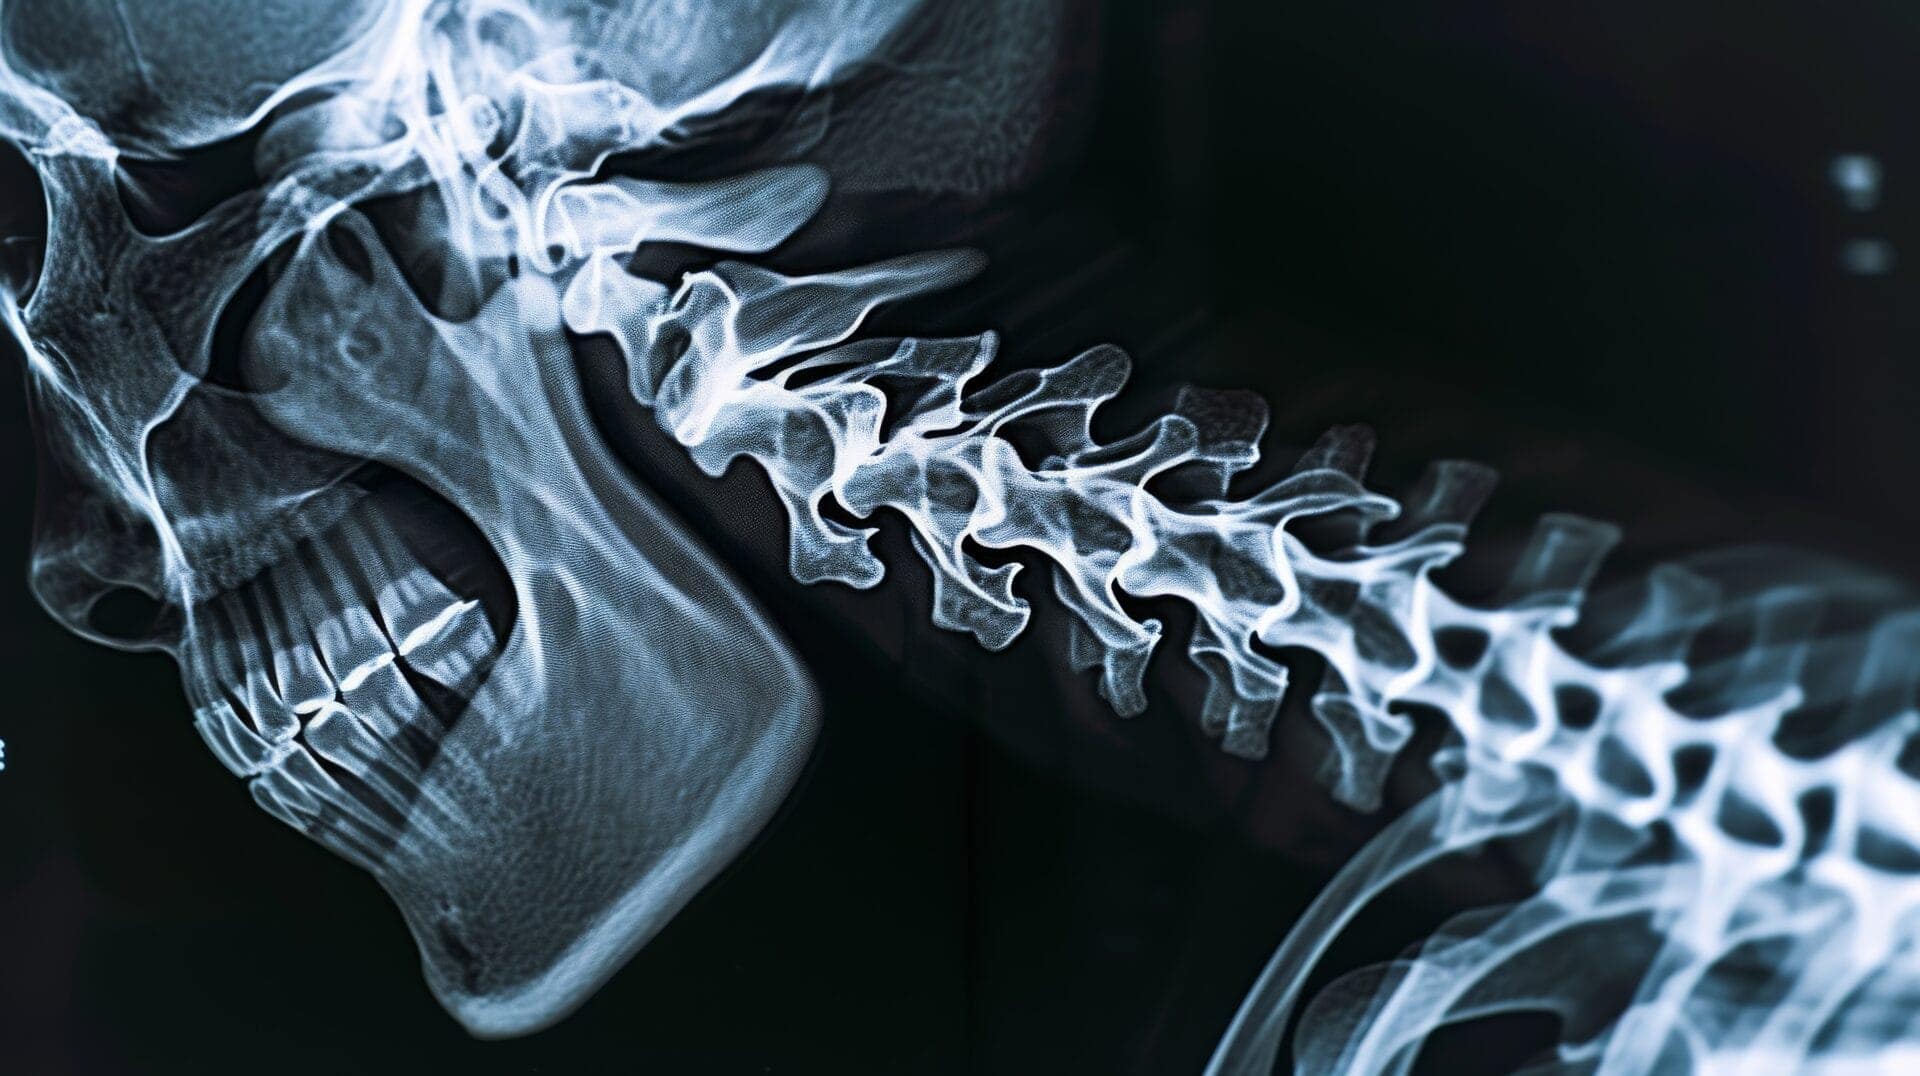

Subluxation of the spine is a term used in chiropractic care to describe a misalignment or dysfunction of a spinal joint. While it’s not a universally recognized medical term, it’s a concept that many chiropractors use to explain potential problems with the spine.

A subluxation, in the context of chiropractic care, refers to a partial dislocation or misalignment of a spinal joint. This doesn’t necessarily mean the joint has completely slipped out of place, but rather that there’s an interference with its normal function. Chiropractors believe that subluxations can disrupt the nervous system’s communication with the body, leading to a range of health problems. These can include pain, stiffness, reduced range of motion, numbness, tingling, and muscle weakness.